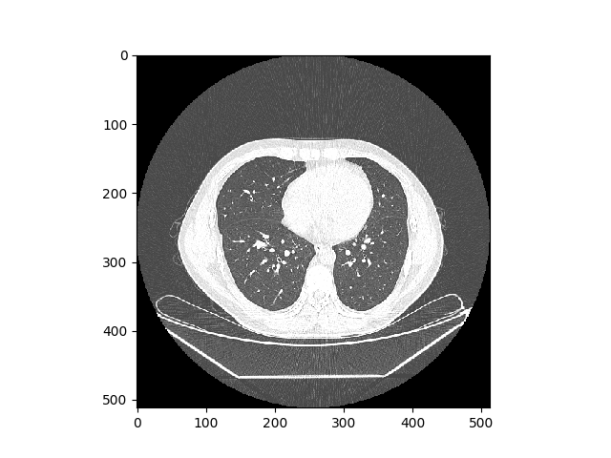

最后将图片转成的数组通过一些Hu像素的转化,使用点运算,将影像值转换为Hu值,然后通过调整vmax和vmin的属性,生成医学概念下的纵膈宽和肺部窗宽图像,对于肺部窗宽,调整之后会比之前呈现更好的亮度,而对于纵膈宽,调整之后会明显呈现一个关键部分突出的图像,如下所示

1210

图 7 肺部窗宽调整前后对比图

132 #肺部窗宽1 300 Hu - 1 700 Hu,窗位-600 Hu  -  -800 Hu,

133

134 ww=1500

135

136 wl=-700

137

138 plt.imshow(hu_ar,cmap='gray',vmin=wl-ww/2,vmax=wl+ww/2,interpolation='nearest')

139

140 plt.savefig('./tmp/12.png')

141

142 plt.show()